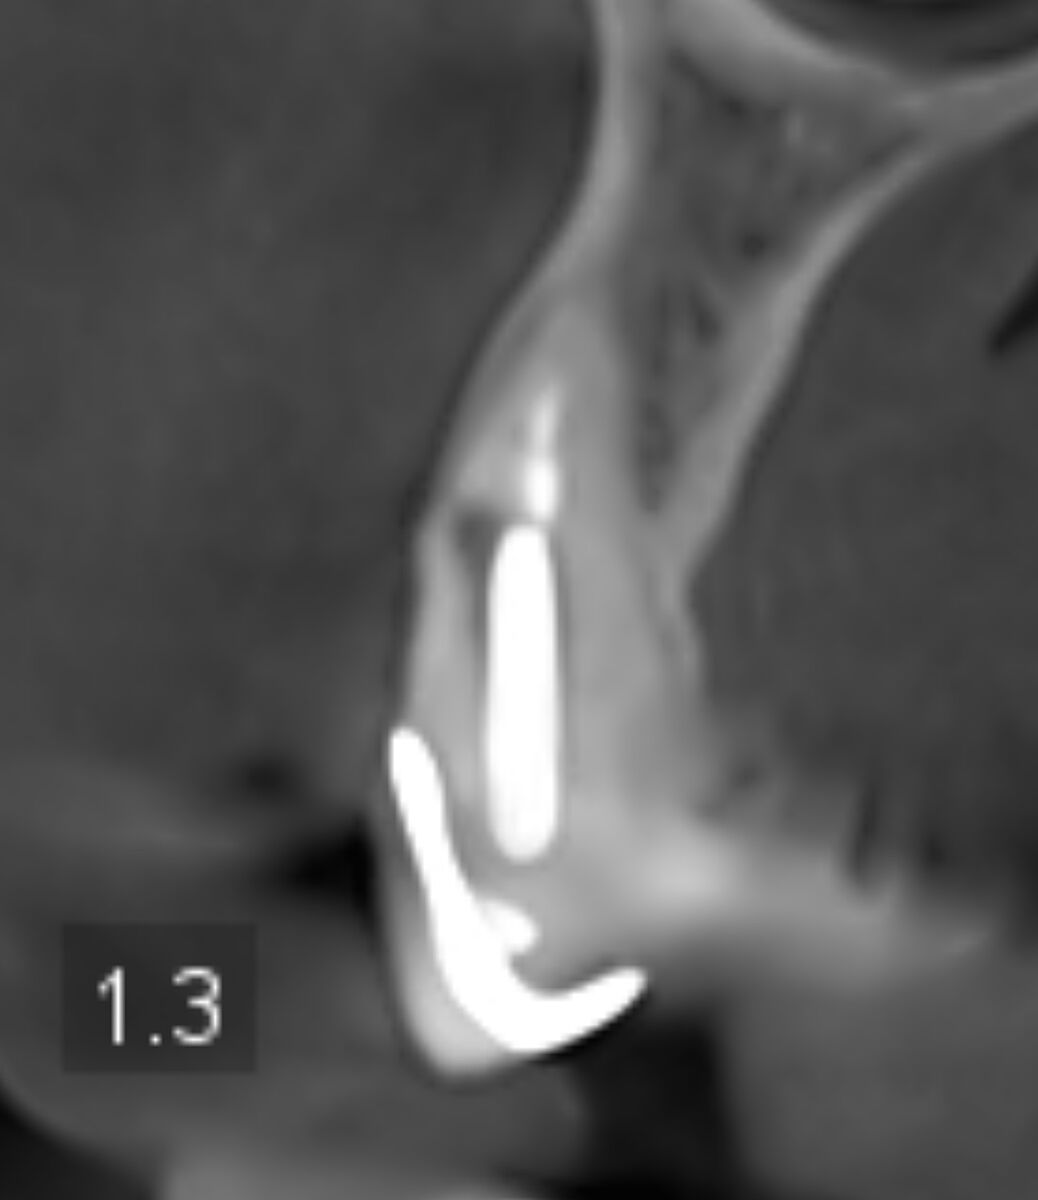

В 70 років приживуться імпланти? Ви суму можете уявити. На знімках канали і корені зубів нормальні, проліковані. Запалень нема. Простіше поміняти старі коронки і поставити незйомні мости на імпланти. По два на одну сторону. Або в такому віці можна дешевий протез, що до ясен прилипає, типу резиновий. Кожні два роки міняти.

Хоч і на штифтах, але корені нормальні, коронка зуба проглядується. У вас навіть прикус правильний при відсутності бокових зубів зверху і знизу. Відстань між щелепами де пусті місця по боках прям ідеально симетричні і не сильно просіли.

Есть здесь зубы нормальные. Есть под вопросом. Т.к. этот снимок надо смотреть полноценно , а не скрины с него. Здесь могут быть и срезы неудачные, и не всегда понятно - артефакты это или на самом деле это есть. + замеры делать надо. И это только рентгенологически... Иногда составляются планы с удалением относительно нормальных зубов для экономии средств и снижения травматичности операции...